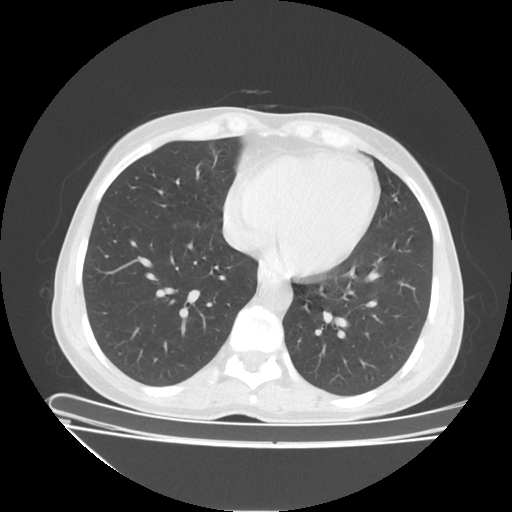

Image Grid

4×3 grid: Rows show different image types (Original NATIVE, Reconstructed NATIVE, Original VENOUS, Generated VENOUS), Columns show windowing techniques (No Window, Lung Window, Mediastinum Window)

Original NATIVE CT scan (input)

Lung window (WL -600, WW 1500 → Low −1350, High +150)

Windowing Parameters

- No Window: Raw intensity values without windowing

- Lung Window: WL -600, WW 1500 → Low −1350, High +150 (optimal for pulmonary structures)

- Mediastinum Window: WL 40, WW 400 → Low −160, High +240 (optimal for soft tissues)